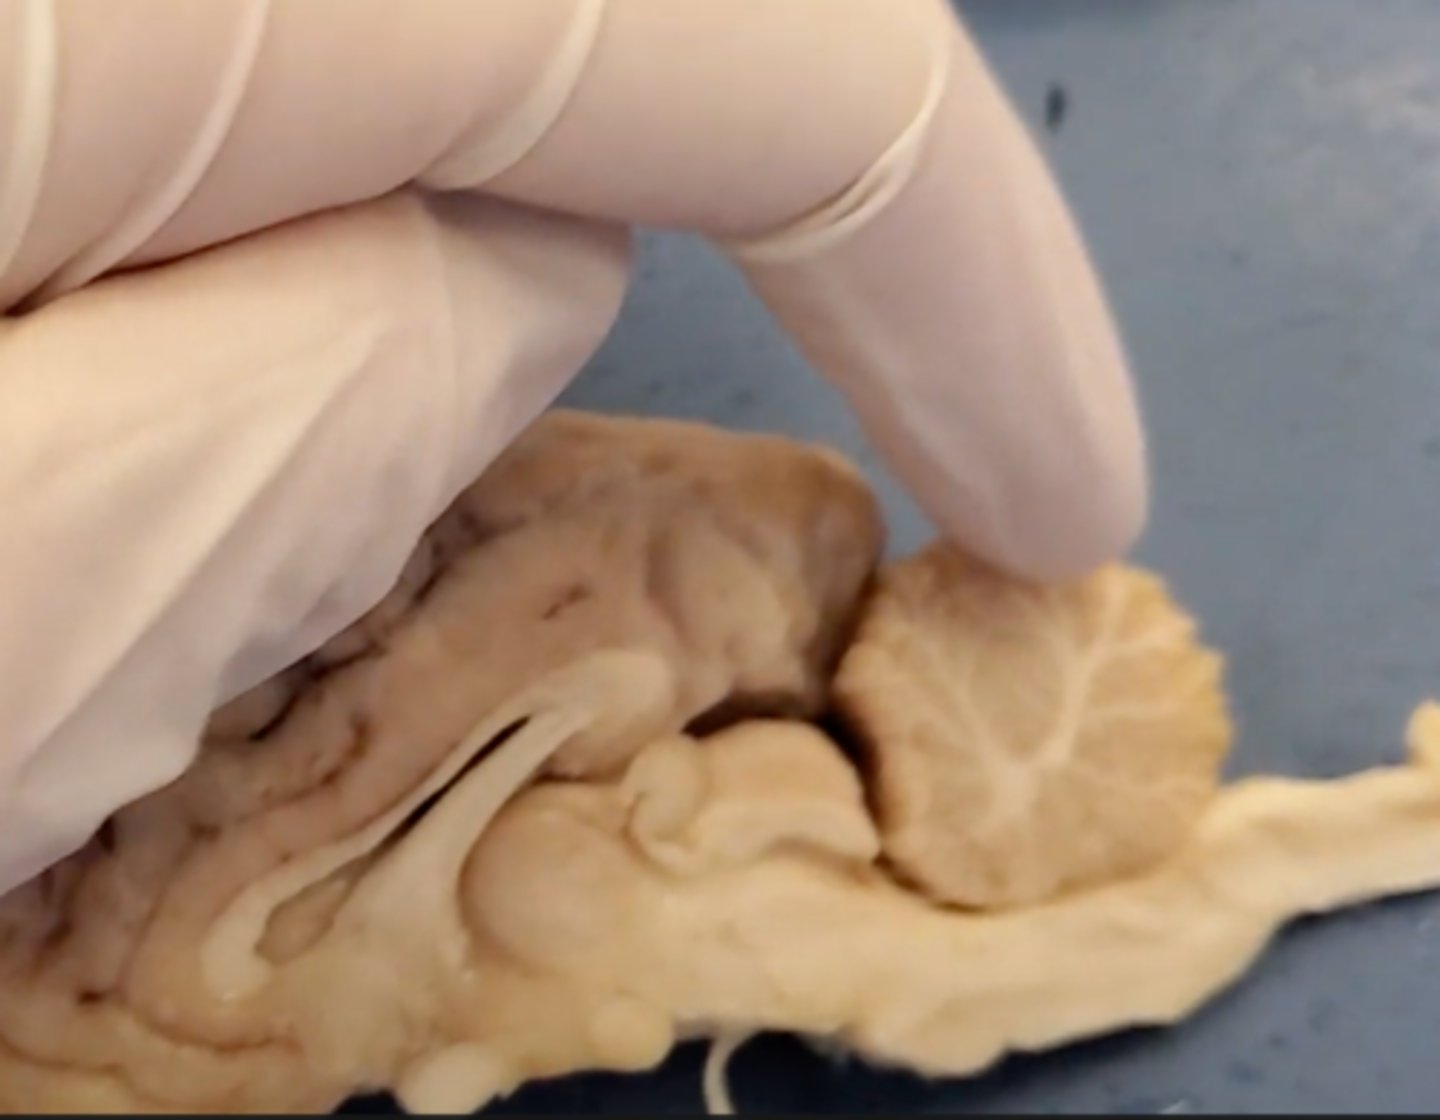

cerebrum

Area of the brain responsible for all voluntary activities of the body

cerebellum

A large structure of the hindbrain that controls fine motor skills.

olfactory bulb

a brain structure located above the nasal cavity beneath the frontal lobes

medula oblongata

part of the brain that controls breathing, heartbeat, and the size of blood vessels

optic chiasma

the crossing of the optic nerves from the two eyes at the base of the brain

optic nerve

the nerve that carries neural impulses from the eye to the brain

corpus callosum

the large band of neural fibers connecting the two brain hemispheres and carrying messages between them